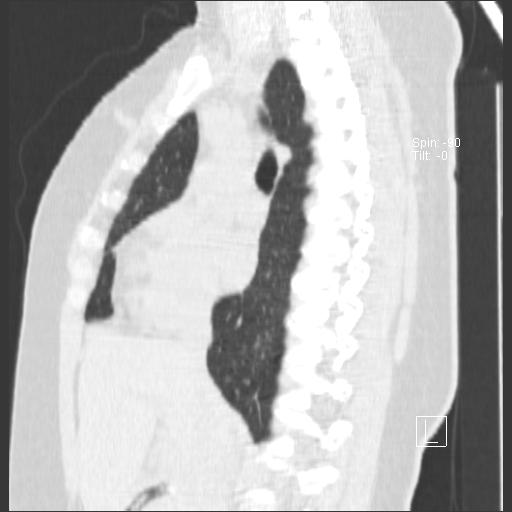

New CT images (without contrast) for 40 year old female with silicone breast implants. Formal diagnosis is expected soon. Images from 2010 can be seen here http://radiology-images.blogspot.com/p/40-year-old-female-silicone-implants.html